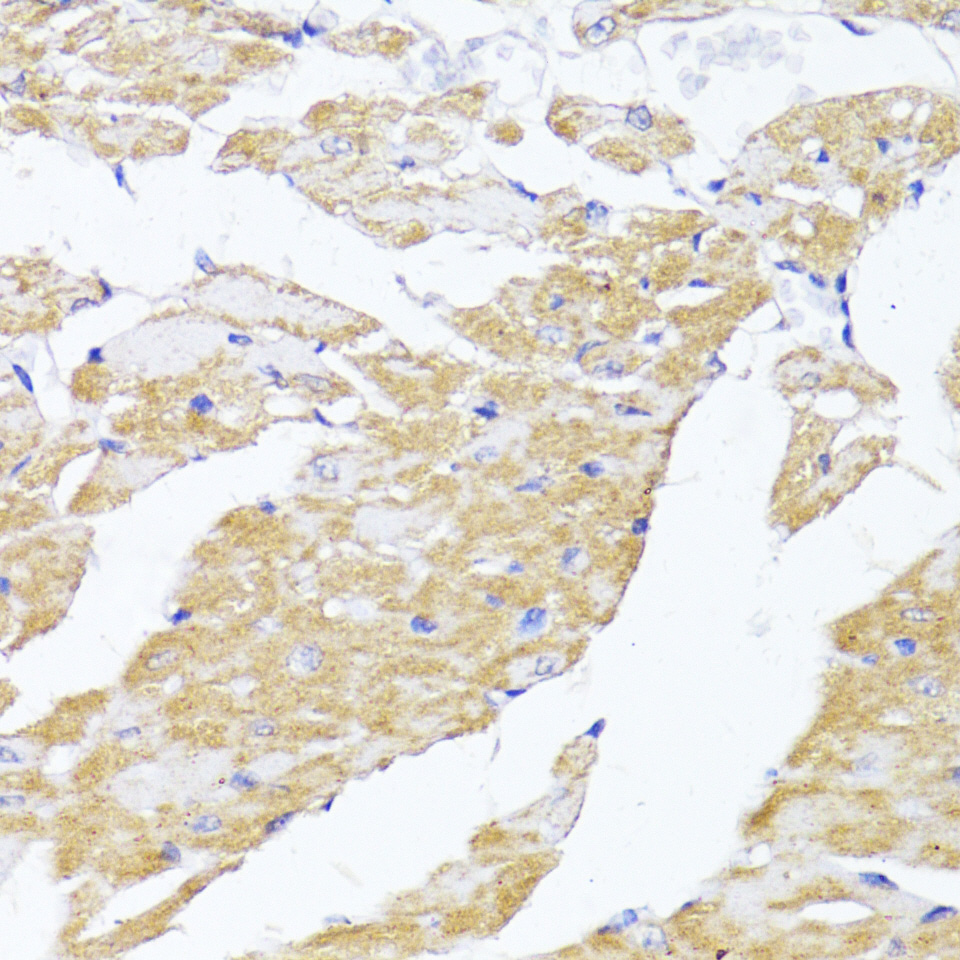

Immunohistochemistry of paraffin-embedded Rat ovary using MAVS antibody.